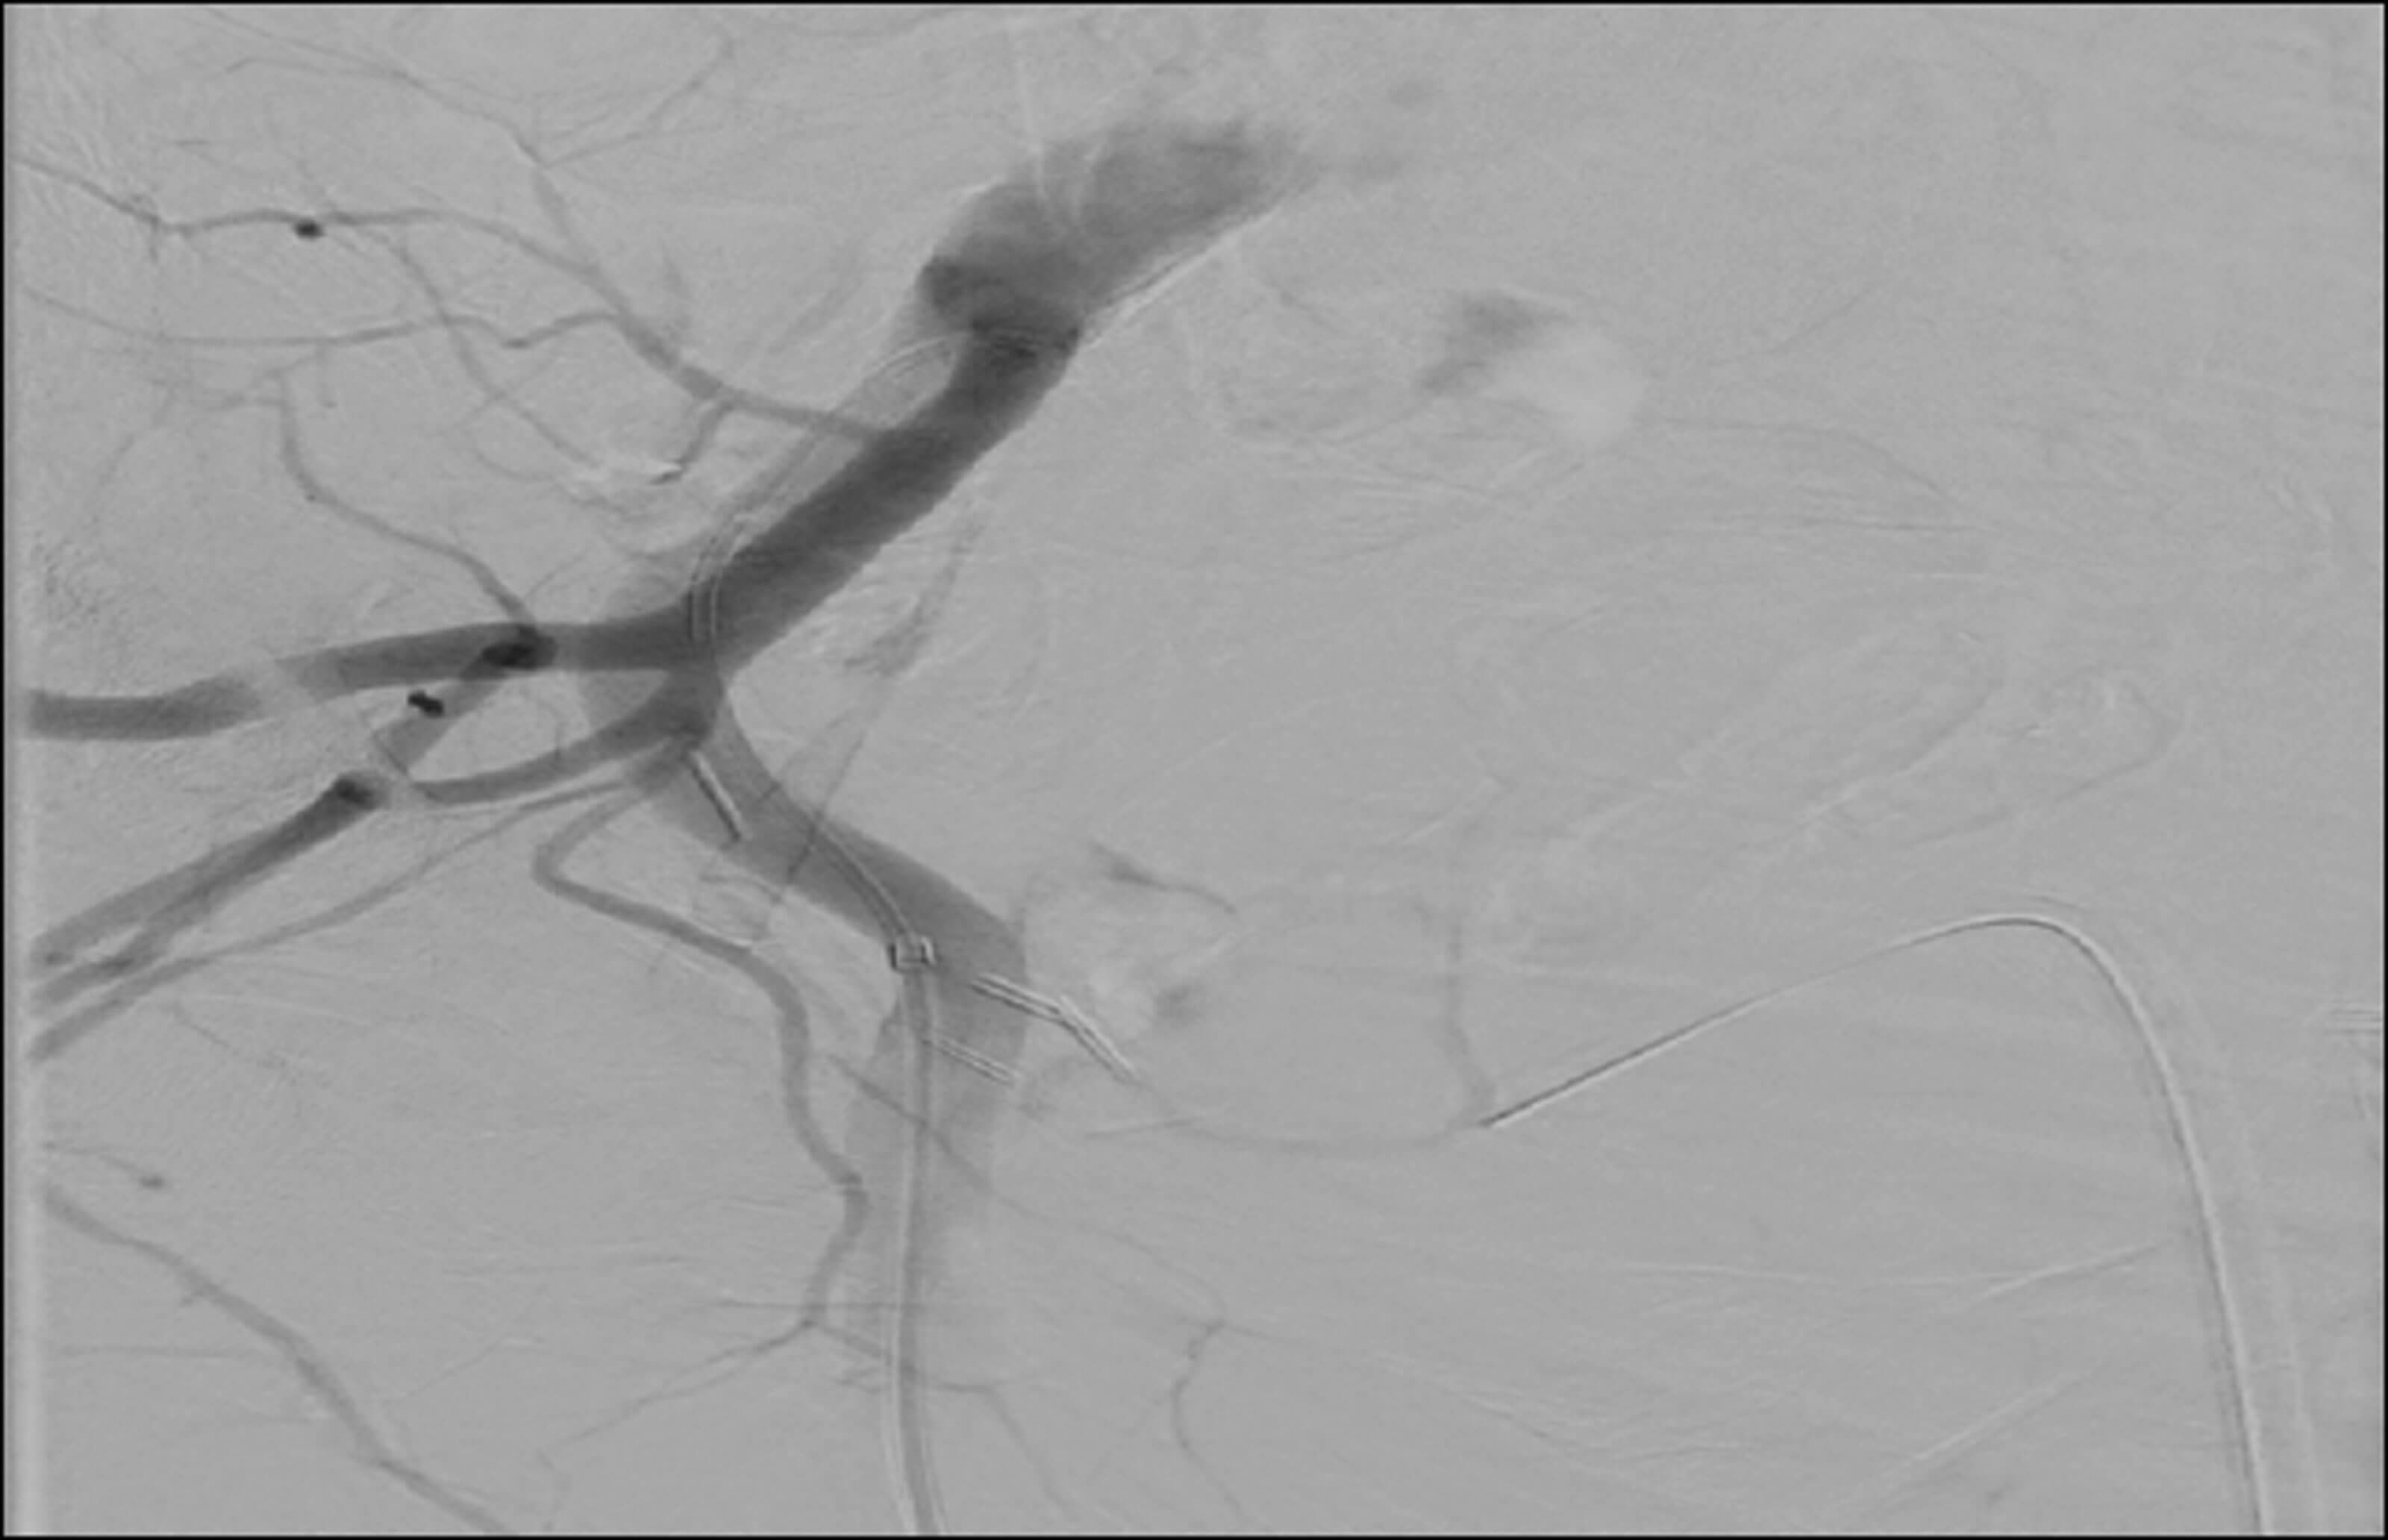

An 86-year-old male presented with visible haematuria and suprapubic pain. He had a history of diabetes, heart failure, benign prostatic hypertrophy, aortic valve replacement, deep vein thrombosis (DVT) and atrial fibrillation (AF) and was anticoagulated on a non-VKA oral anticoagulant (NOAC). Despite conservative measures of washouts and irrigation via a three-way catheter, the bleeding continued. Using the arteriogram, the source of bleeding was identified, with interventional radiological guidance. Interventional radiology then attempted prostate artery embolisation to contain the bleeding. The left prostatic artery was identified, cannulated and embolised, the right prostate artery failed cannulation due to the presence of an atherosclerotic plaque (Figure 1).

Figure 1.